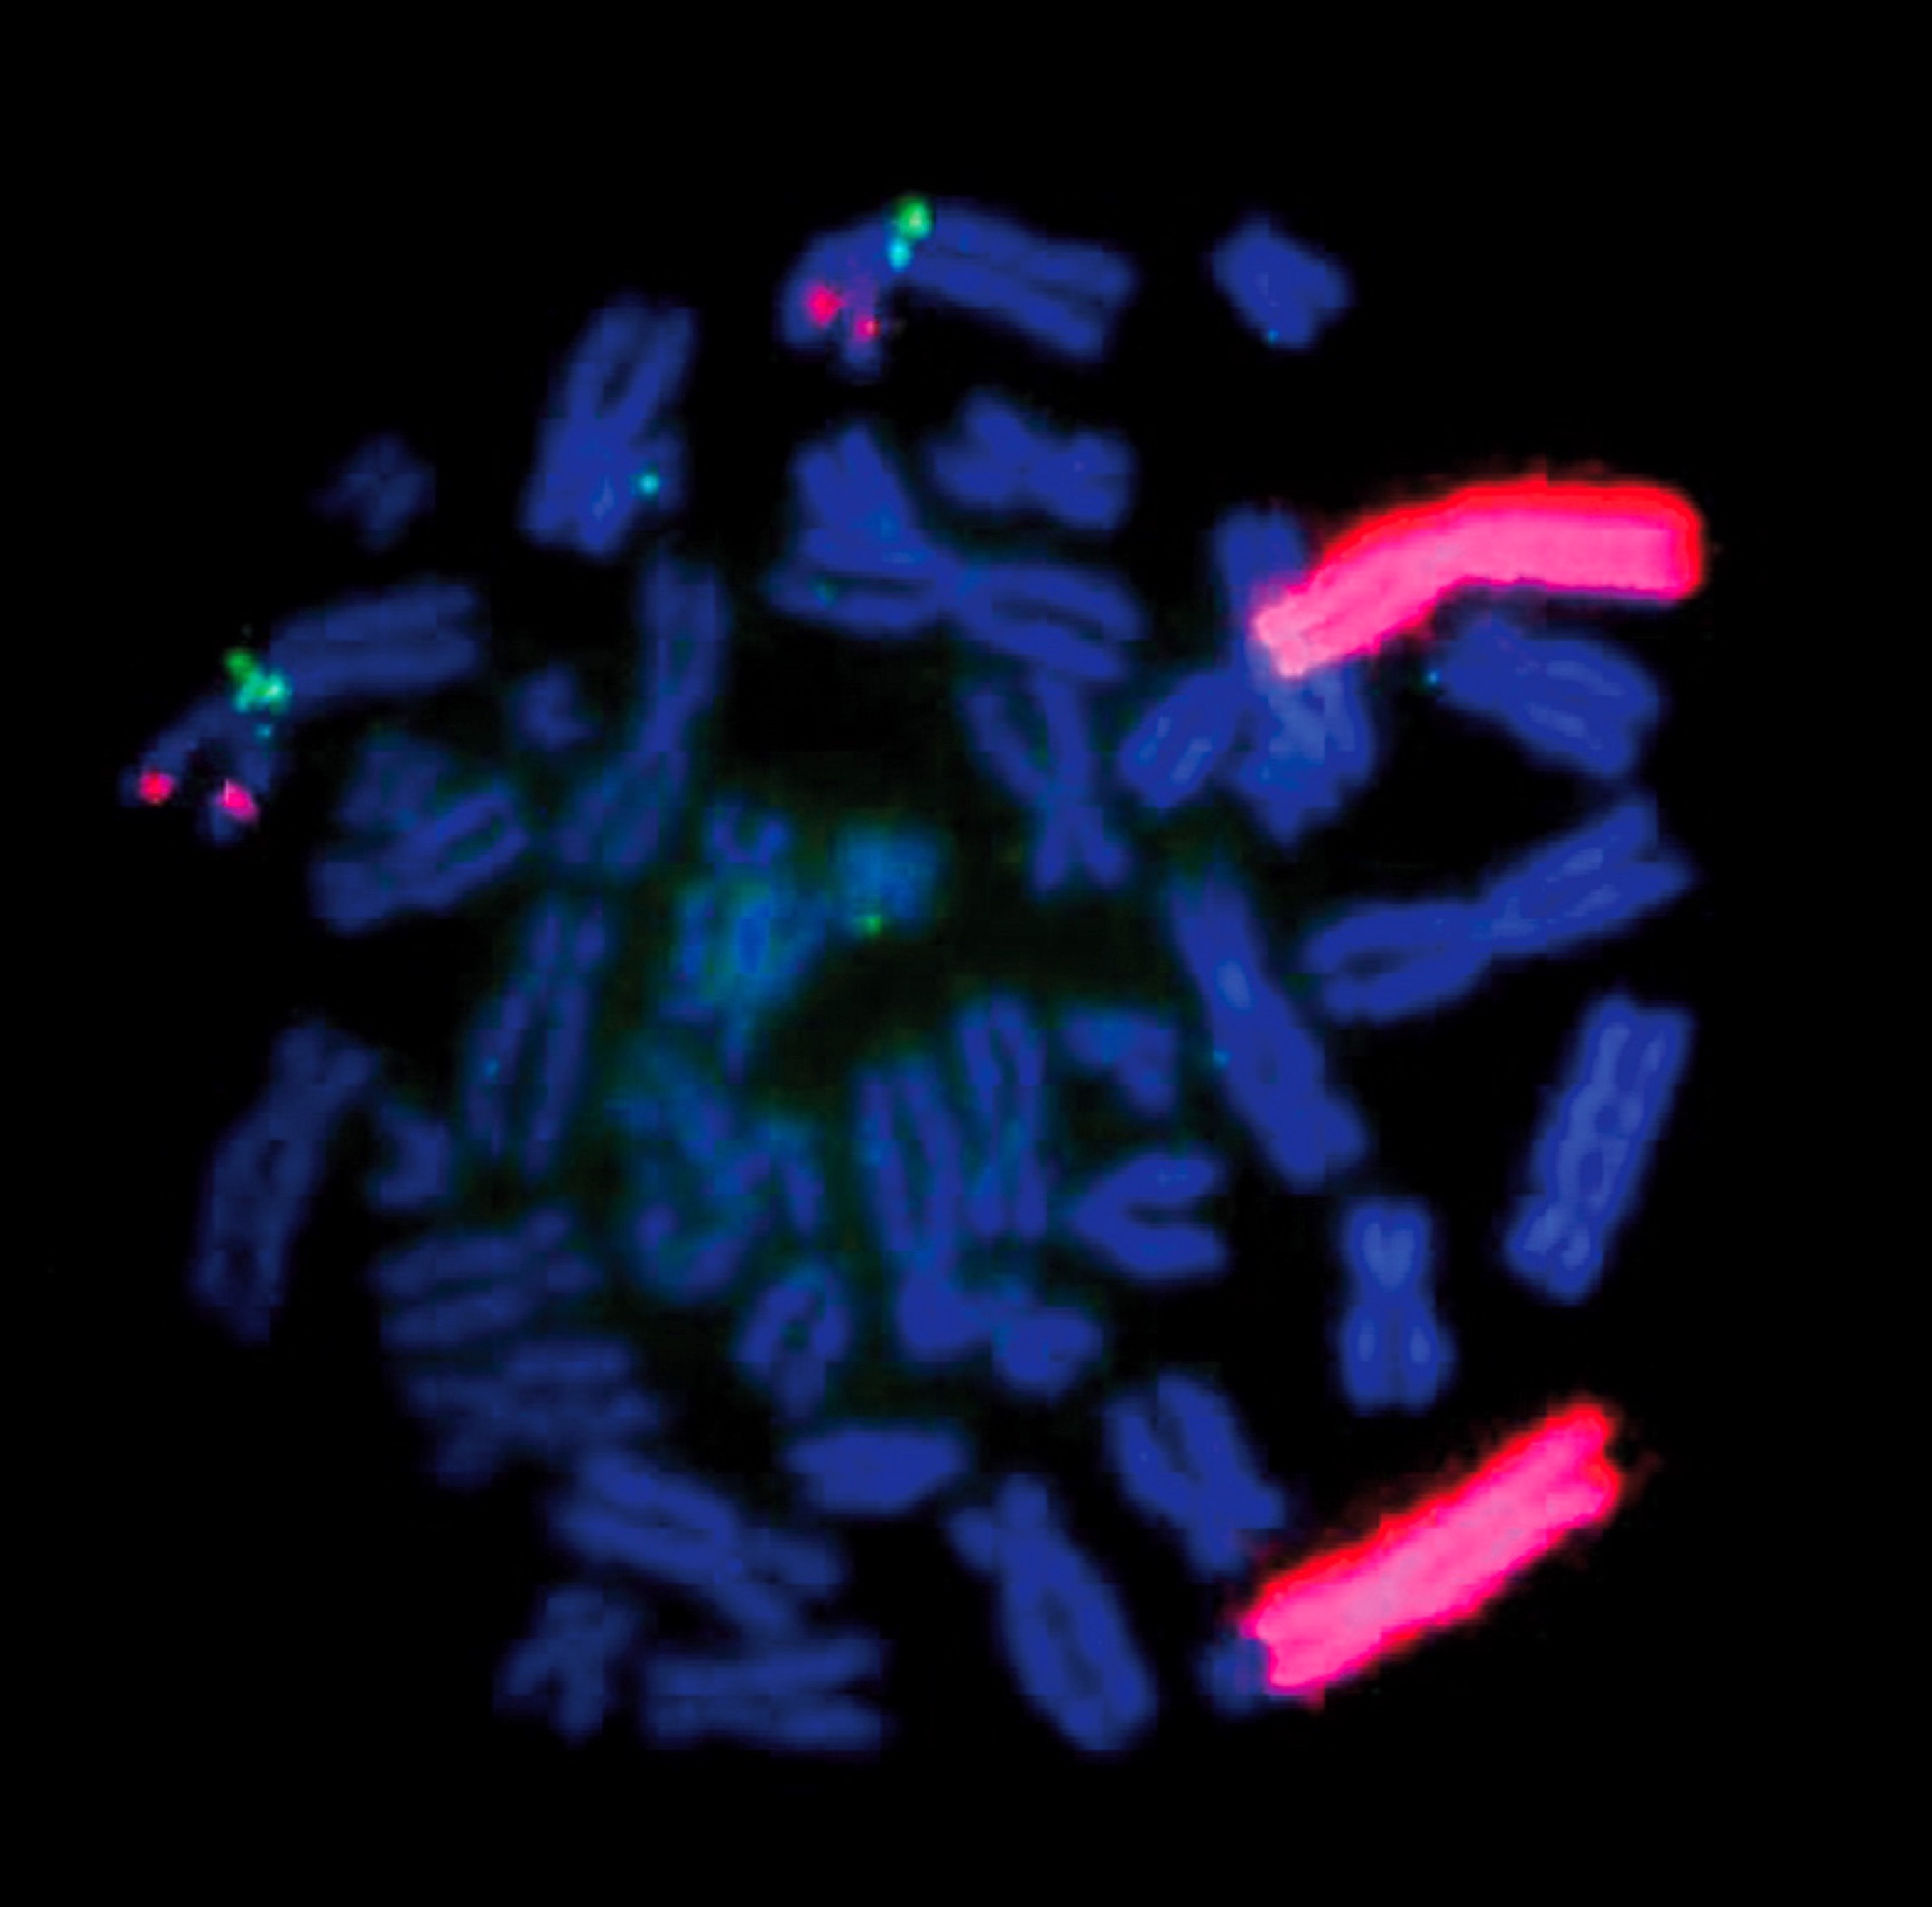

Molecular / cytogenetics description

- Considered molecularly heterogeneous but much of genetic basis remains unexplained (Cancer 2003;98:2274)

- ALK gene mutations have been implicated in some cases of ganglioneuroblastoma (Am J Pathol 2012;180:1223)

- Ganglioneuroblastoma, stroma rich, nodular subtype, is considered a composite tumor consisting of separate clones (less aggressive stroma rich component; nodular component consisting of a favorable / unfavorable / both clones) (Cancer 2003;98:2274)